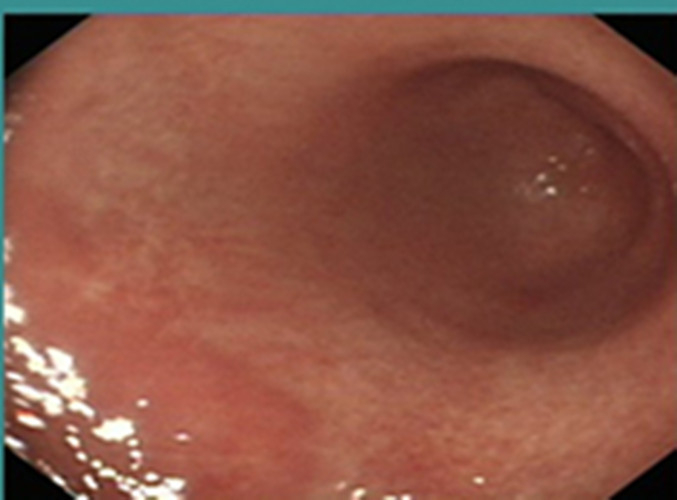

慢性胃炎圖片

慢性胃炎

慢性胃炎的

成人慢性胃炎

中型淺表萎縮慢性胃炎

萎縮淺表性慢性胃炎

萎縮性的慢性胃炎

萎縮性慢性胃炎

萎縮慢性胃炎

萎縮出血性慢性胃炎

輕型淺錶慢性胃炎

輕型淺表型慢性胃炎

縮的慢性胃炎

淺表型慢性胃炎怕

淺表型慢性胃炎

淺表型慢性胃炎萎縮

淺表型糜爛出血慢性胃炎

淺表型糜爛慢性胃炎

輕型慢性胃炎

淺表型慢性胃炎發發

淺表型慢性胃炎好